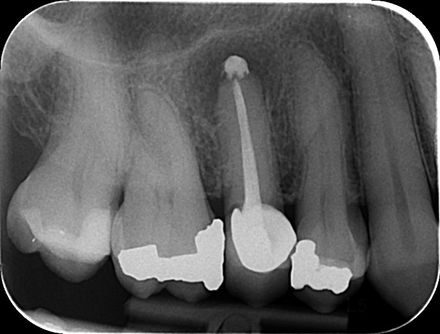

When a patient receives trauma to their teeth, the management is very important in improving the success of treatment.

This young gentleman had an accident at rugby that displaced the tooth. The tooth was reinserted, a “flexible” splint applied and as the tooth died, a root canal filling using Mineral Trioxide Aggregate (MTA) was used.